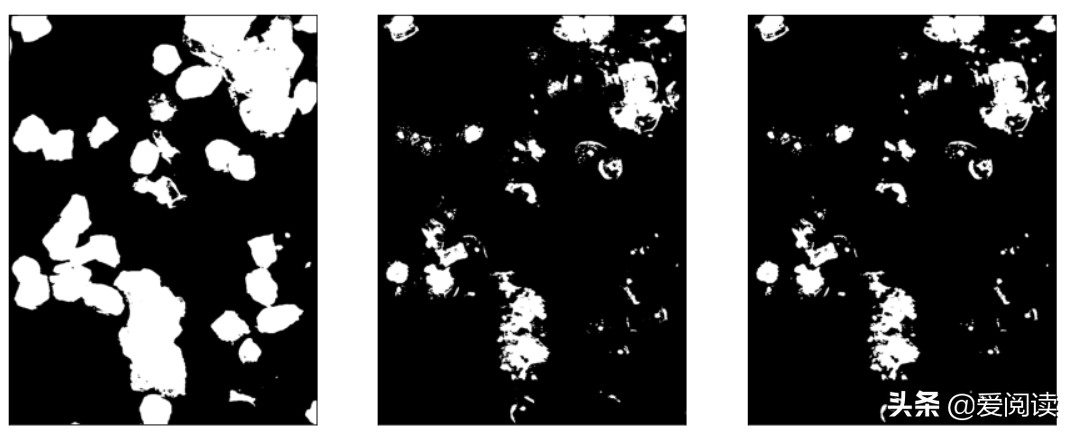

分割分割及过滤:

你试过吗?图像(细胞)分割

细胞区域初步分割结果:

fig = plt.figure(figsize=(15,8))

plt.subplot(121),plt.imshow(bw_nucleus_s, 'gray') , plt.xticks([]),plt.yticks([])

plt.subplot(122),plt.imshow(bw_nucleus, 'gray'), plt.xticks([]),plt.yticks([])

plt.show()

最终细胞核分割定位效果:左边是原图,右边是细胞核行为结果: